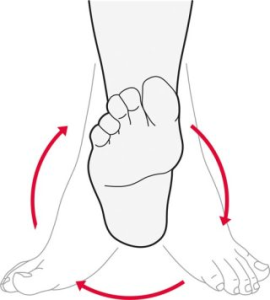

- چرخش مچ پا

مطابق تصویر شماره ۸ چرخش مچ به انعطاف آن کمک میکند تا بتواند در تمامی جهات حرکت کند.

روی یک صندلی بنشینید و پای آسیب دیده را از زمین بلند کنید. به آرامی مچ پا را در جهت عقربه ساعت پنج مرتبه بچرخانید.مچ پا را در جهت خلاف عقربه ساعت پنج مرتبه بچرخانید.

اگر در هر دو پا دچار سندروم تونل تارسال هستید، این کار را برای هر دو پا انجام دهید. در طول روز دو یا سه بار این حرکت را تکرار کنید تا زمانی که در ناحیه مچ و کف پا احساس بهتری داشته باشید.

تصویر شماره ۸، تمرین شماره ۳: چرخش مچ پا